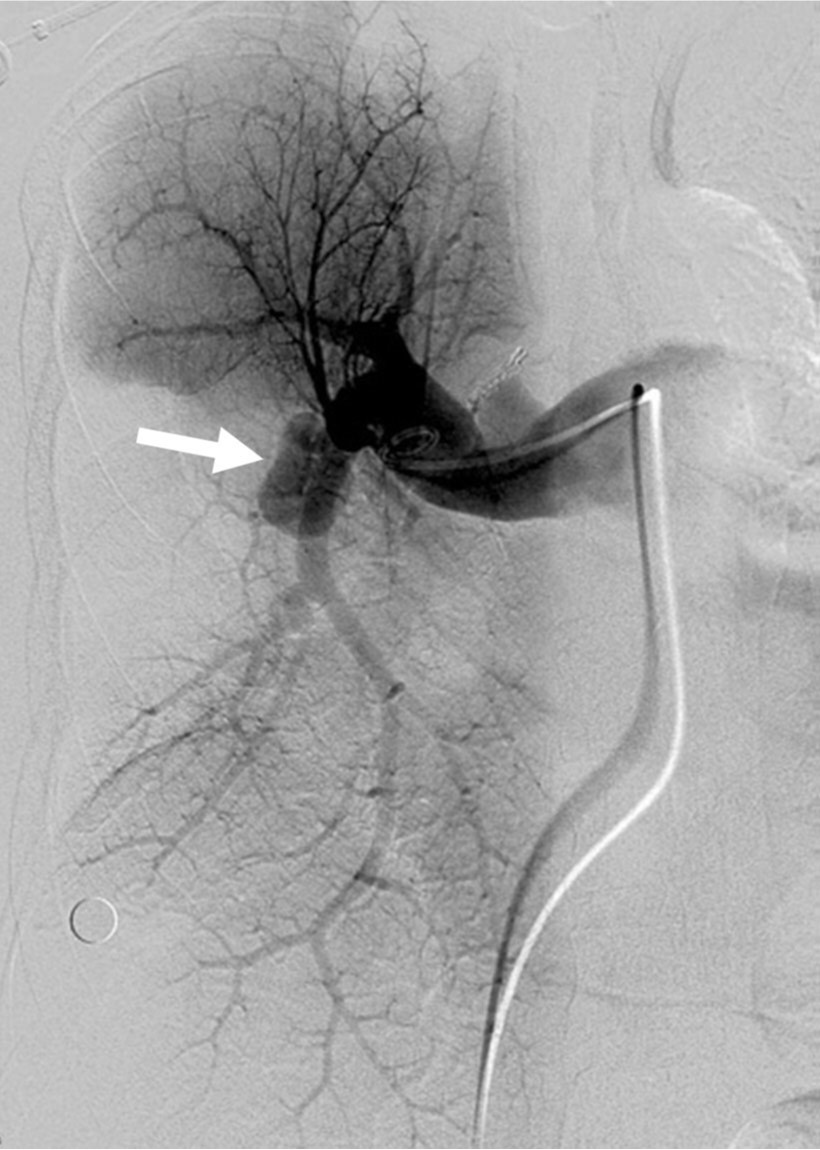

Fig. 2.

Fig. 2. Right pulmonary angiogram shows a pseudoaneurysm (arrow) at the proximal part of the right lower pulmonary artery.